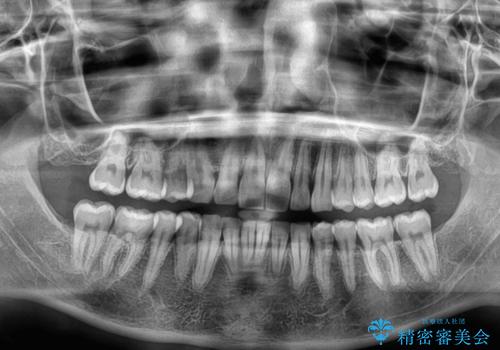

深い咬み合わせと前歯のデコボコ ワイヤー装置での抜歯矯正

- 深い咬み合わせと前歯のデコボコを改善したいとのことで来院された患者様です。

口元の突出感はないものの、上顎前歯のデコボコが著しく、右側の咬み合わせがずれていたため、上顎右側第一小臼歯1本を抜歯することとしました。

咬合力が非常に強く、抜歯したスペースがなかなか閉じないであろうことは予想できましたが、思っていた以上に期間がかかりました。

前歯のすり減りも著しかったため、仕上げの位置の調整にも期間を要しました。